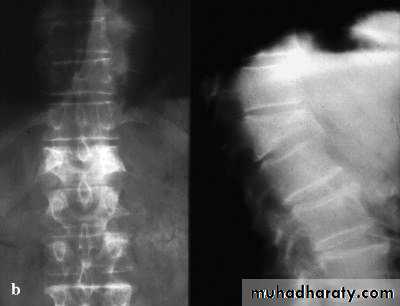

Thoraco-Lumbar fractures

Spinal cord terminates at L1/2 disc in adultL2/3 in a child

50% of injuries occur at Thoraco-lumbar junction.

Common fractures:

Wedge fracture (flexion/compression).

Burst (compression).

Chance (flexion/distraction).

Wedge fracture

Burst fracture

Chance fracture

Fracture dislocation